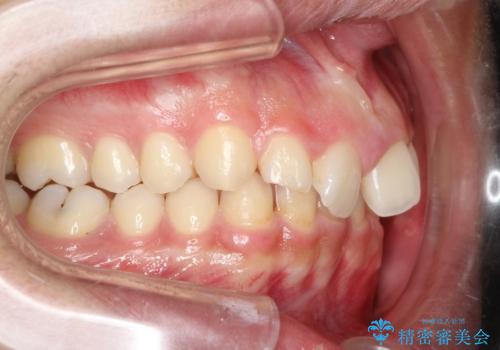

初診時の歯並びの状態としては、上下ともに前歯部の中等度のがたつきがあり、前歯には正中離開があり過蓋咬合を呈してい状態でした。

また奥歯の噛み合わせのズレもあり、特に左は顕著に認められました。